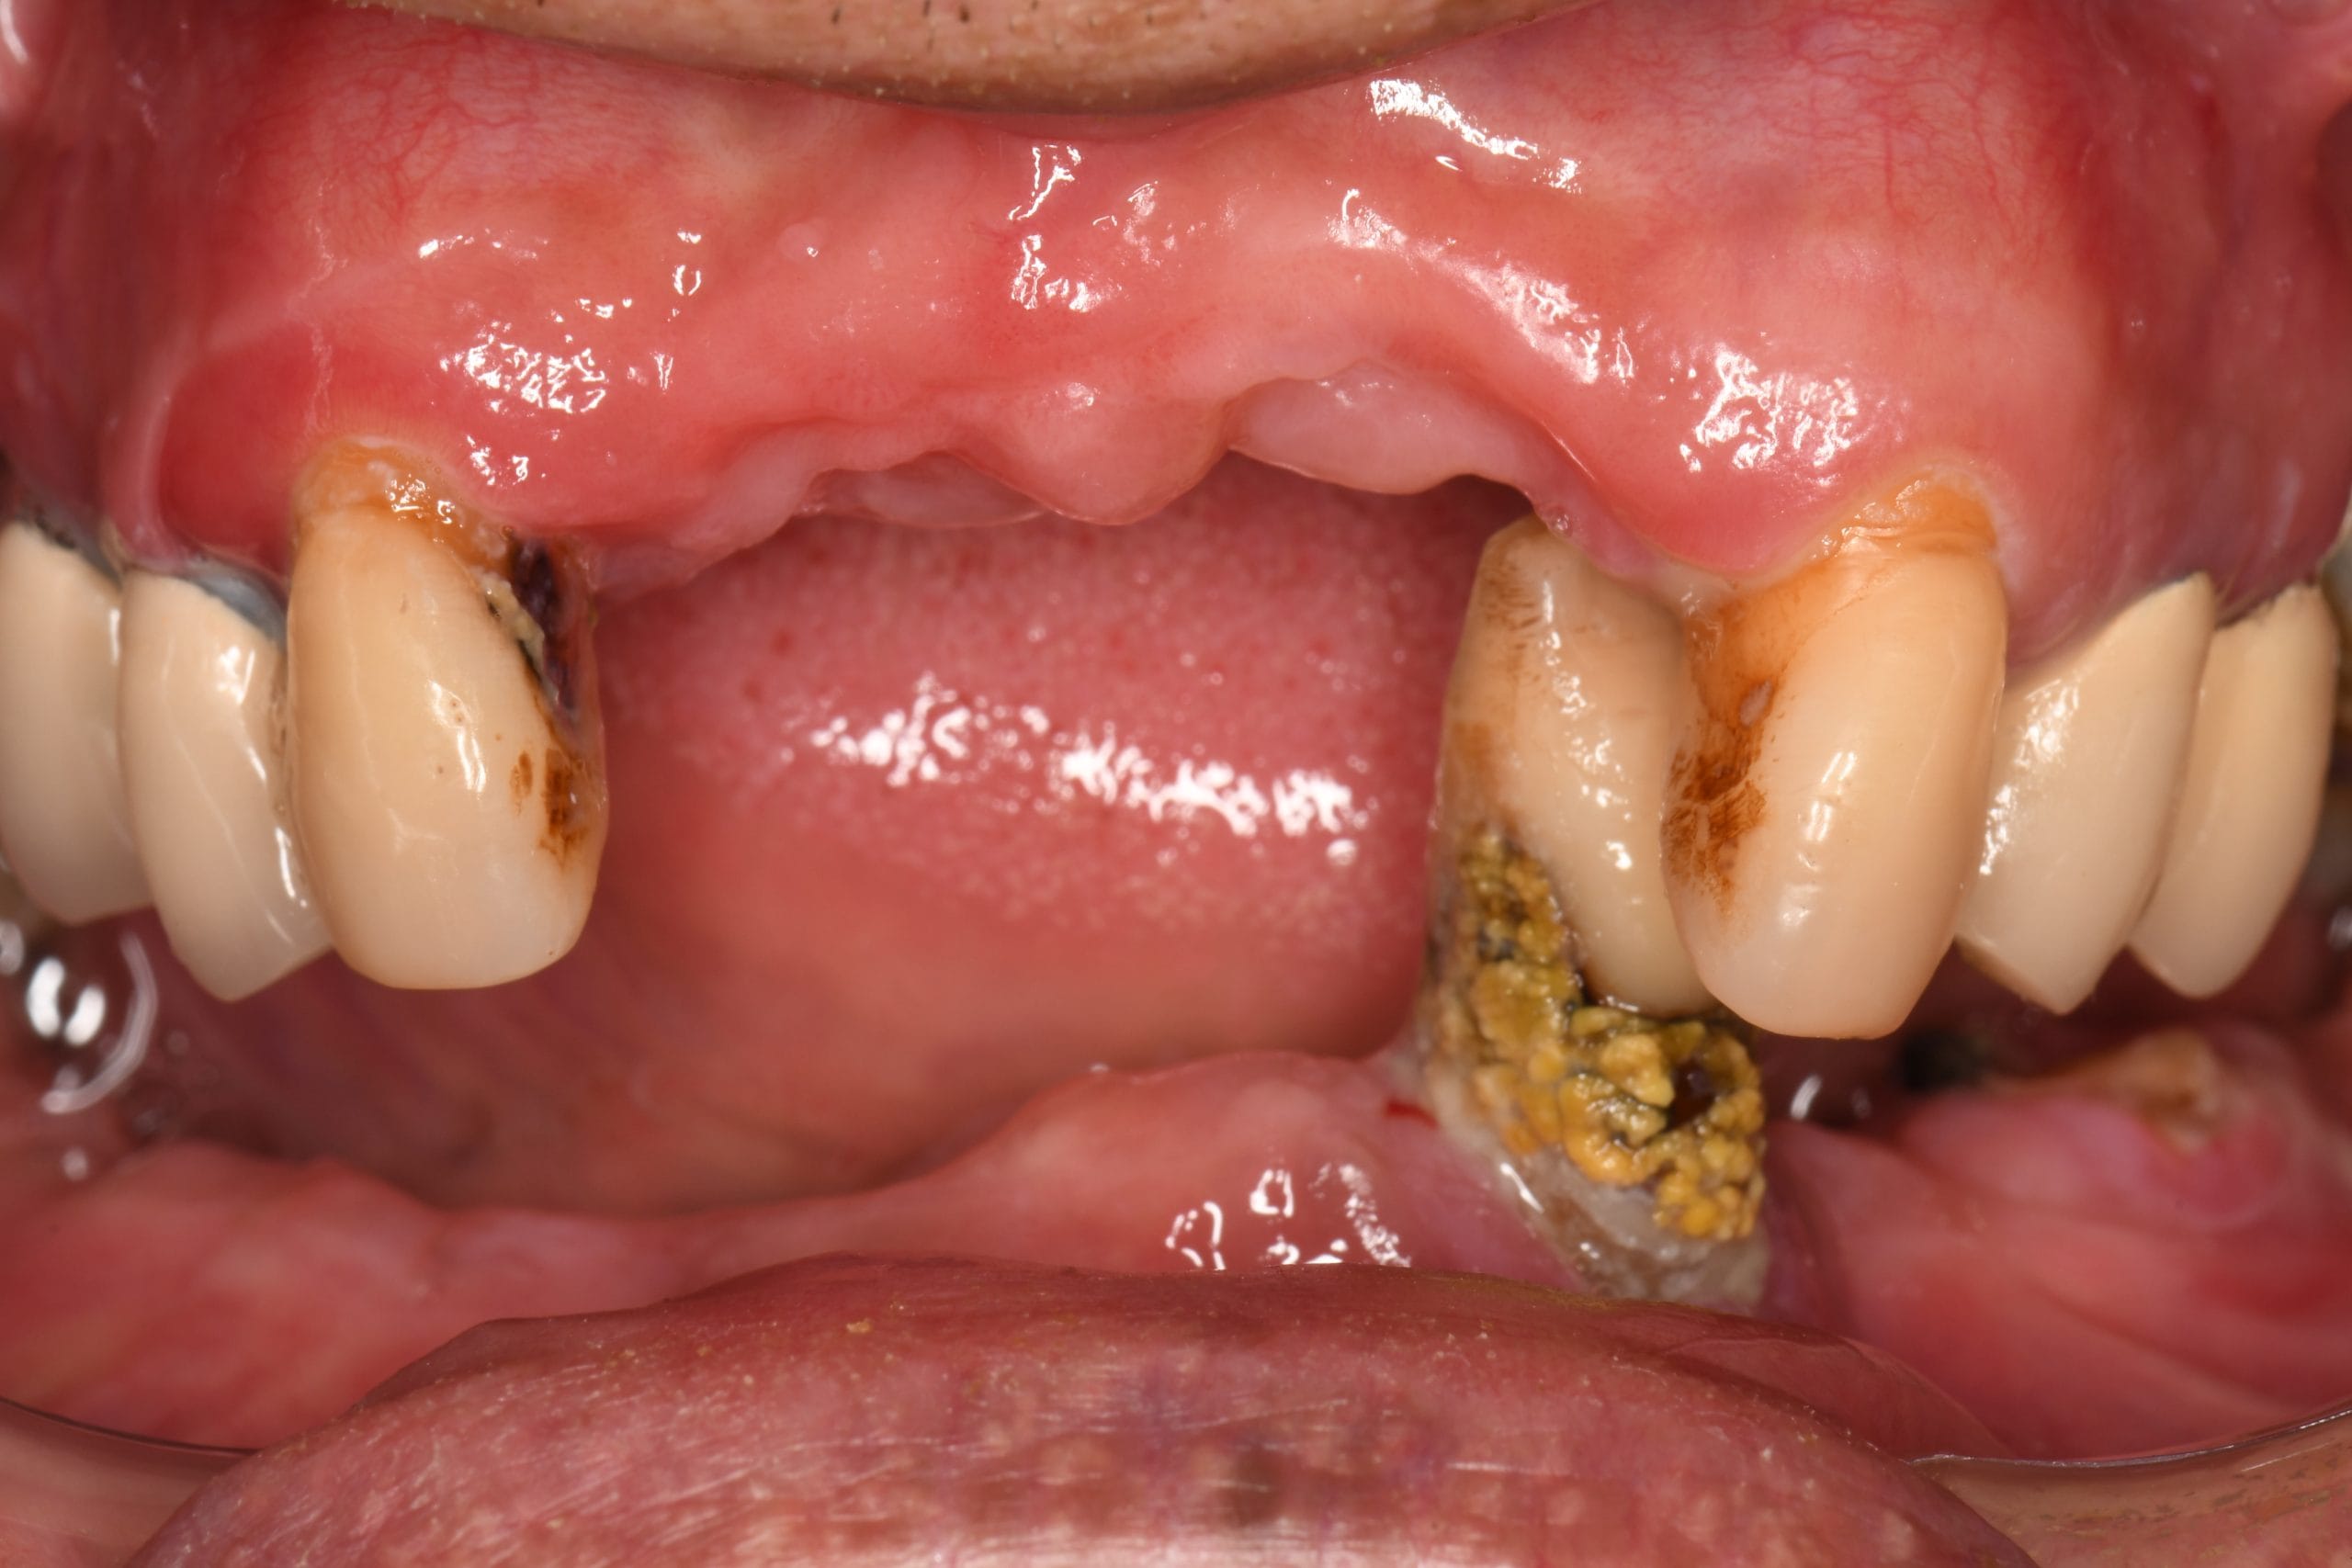

54歲患者L先生因患有糖尿病,上下顎缺牙長期佩戴活動假牙,後來其他牙齒的牙周狀況越來越差,陸續拔除到下顎剩下1顆完整齒質,活動假牙鬆動至不堪使用;L先生想尋求根本的治療方法,故到藝心諮詢全口重建。

下顎僅剩下1顆牙齒(不含智齒),已勾不住活動假牙,長期只能將食物剪小塊食用,無法正常咬合及咀嚼食物,進食很不方便。

(左上)無佩戴活動假牙時;(右上)患者配戴原有的上顎及下顎活動假牙。